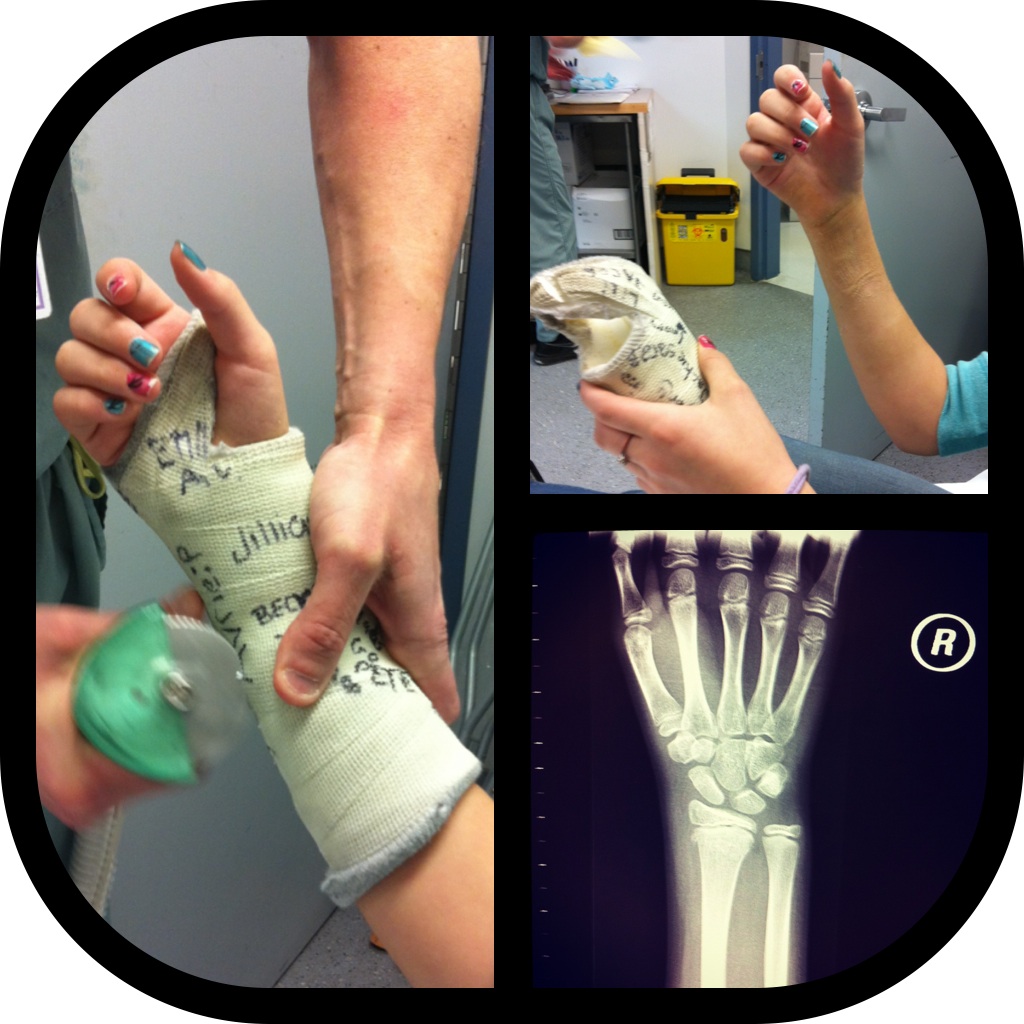

On Friday, Emma had her cast removed… finally! 6 weeks has felt like several months to her. She injured herself prior to Christmas break, running backwards in P.E. class. She’s super sad that she can’t join the volleyball team this year.